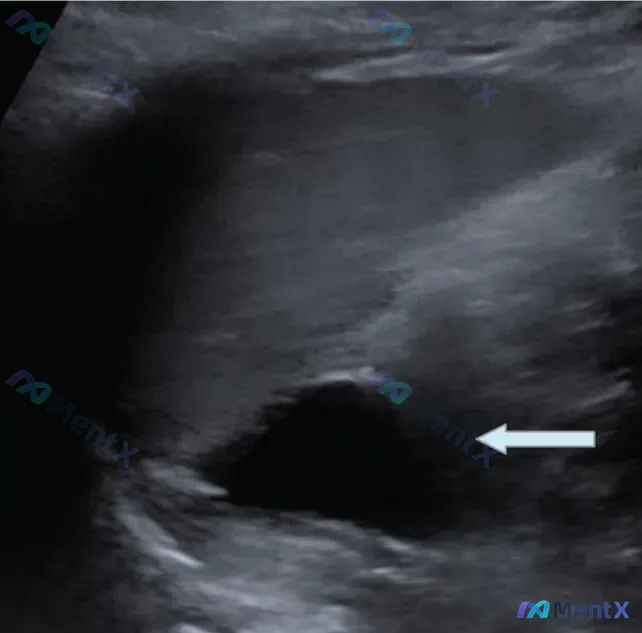

整理了一个出生1个月婴儿的左肾上腺区超声病例,感觉定位和特征结合起来挺有意思,思路分享给大家。 病例基本情况 - 检查时间:出生后1个月 - 检查部位:左侧肾上腺 - 关键影像表现: 1. 病灶定位:最初容易被误认为肝脏左叶邻近区域(超声易混淆,先锚定「左侧肾上腺」为检查目标 2. 病灶形态:类圆形...